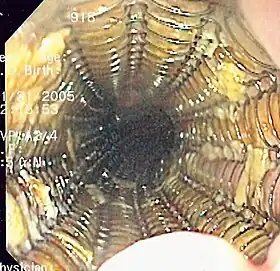

An esophageal stent is a stent (tube) placed in the esophagus to keep a blocked area open so the patient can swallow soft food and liquids. They are effective in the treatment of conditions causing intrinsic esophageal obstruction or external esophageal compression. For the palliative treatment of esophageal cancer most esophageal stents are self-expandable metallic stents. For benign esophageal disease such as refractory esophageal strictures, plastic stents are available. Common complications include chest pain, overgrowth of tissue around the stent and stent migration. Esophageal stents may also be used to staunch the bleeding of esophageal varices.[1]

Esophageal stents are placed using endoscopy when after the tip of the endoscope is positioned above the area to be stented, then guidewire is passed through the obstruction into the stomach. The endoscope is withdrawn and using the guidewire with either fluoroscopic or endoscopic guidance the stent is passed down the guidewire to the affected area of the esophagus and deployed. Finally the guidewire is removed and the stent is left to fully expand over the next 2–3 days.